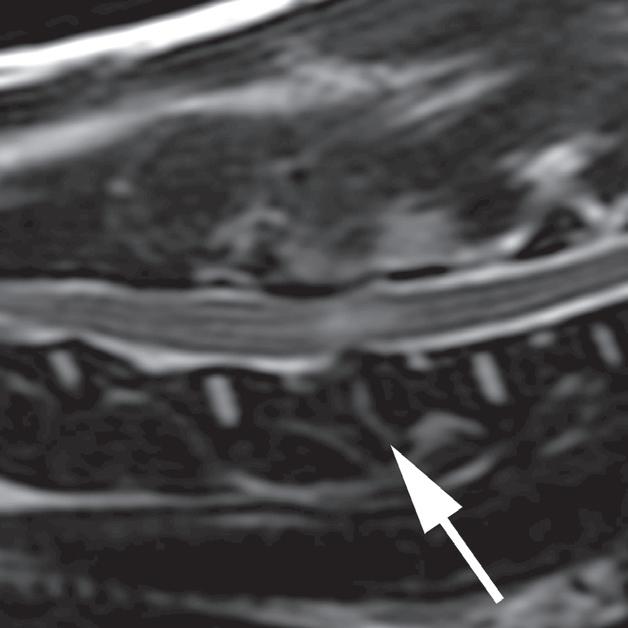

Rycina

3.2.8. Podwichnięcie kręgów szyjnych ze złamaniem wyrostka stawowego (pies) TK i MR

Badania wykonano u 5-letniej samicy mieszańca w typie teriera, która została pogryziona w okolicy szyjnej przez większego psa tego samego dnia, w którym wykonano badania. Podczas wizyty u psa zaobserwowano deficyty neurologiczne z neuroanatomiczną lokalizacją w obrębie C6–T2. Radiogramy przeglądowe ukazały grzbietowe podwichnięcie kręgu C7 względem C6 oraz zwężenie przestrzeni międzykręgowej C6–C7 (a – grot strzałki). Podobne zmiany uwidoczniono na obrazach TK w projekcji strzałkowej i 3D (b, f – grot strzałki). Dodatkowo stwierdzono wieloodłamowe złamanie z przemieszczeniem prawego doczaszkowego wyrostka stawowego kręgu C7 (c–e – strzałka). Dla porównania przedstawiono prawidłowy lewy wyrostek stawowy (f – strzałka). W badaniu MR przestrzeń międzykręgowa C6–C7 była zwężona i wykazywała obniżoną intensywność sygnału w obrazach T2-zależnych (i – strzałka), a przemieszczony materiał dyskowy znajdował się w prawej dobrzusznej części kanału kręgowego (g, h – grot strzałki). W obrazach występują cechy ucisku na rdzeń kręgowy (g–i) oraz zwiększona intensywność sygnału w sekwencji T2-zależnej w obrębie rdzenia na poziomie C6–C7 (h, i), co wskazuje na jego uszkodzenie wewnętrzne. Materiał dyskowy został chirurgicznie usunięty z kanału kręgowego, a podwichnięcie zredukowano i ustabilizowano operacyjnie